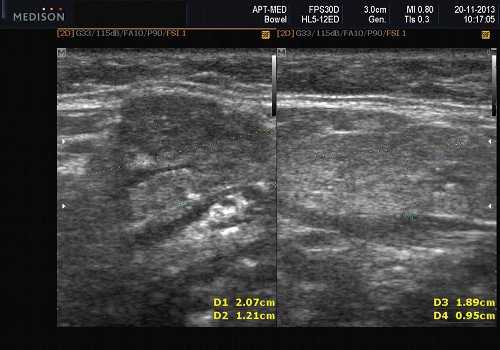

Теория и практический опыт в ультразвуковой диагностике патологии слюнных желез

В отечественной и зарубежной литературе встречается много работ, посвященных сиалогии (от греч. Sialon - слюна и logos - учение) - науке о заболеваниях и повреждениях слюнных желез, методах их диагностики и лечения. По данным разных авторов, на долю заболеваний слюнных желез приходится до 24% всей стоматологической патологии. В настоящее время в клинической практике наиболее часто встречаются дистрофические, воспалительные заболевания слюнных желез (сиалоаденозы, сиалоадениты), а также опухоли и врожденные пороки развития слюнных желез. Кроме того, патологические изменения слюнных желез часто сопутствуют другим заболеваниям (сахарный диабет, бронхоэктатическая болезнь, саркоидоз, цирроз печени, гипертриглицеридемия, лимфогранулематоз и др.).

- ультразвуковой метод (является наиболее доступным, безопасным и информативным в процессе дифференциальной диагностики патологического состояния слюнных желез).

Патология слюнных желез

- обструктивные сиаладениты, развивающиеся при затруднении оттока слюны при обструкции выводного протока камнем (рис. 5-7) или сгустившимся секретом, а также вследствие рубцового стеноза протока. По распространенности процесса различают очаговый, диффузный сиаладениты и сиалодохит - воспаление выводного протока. Течение процесса может быть острым и хроническим;

Рис. 5. Камень протока поднижнечелюстной слюнной железы.

Рис. 6. Камень в паренхиме поднижнечелюстной слюнной железы.

Рис. 7. Камень в протоке поднижнечелюстной слюнной железы.

Подводя итог, хочется отметить, что ультразвуковое исследование с применением допплерографии во многих наших наблюдениях помогало точно определить характер патологического процесса в СЖ. Однако этот метод диагностики не позволяет однозначно подтвердить или опровергнуть злокачественный характер образования слюнных желез.